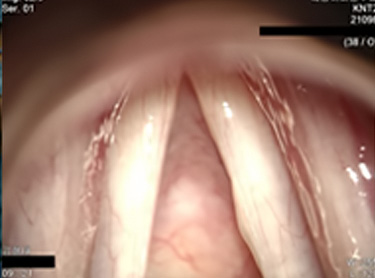

먼저 성대앞쪽의 1/3 부분의 점막을 제거한 후 성대근육을 꼬매주는 방법으로 성대의 진동길이 만큼 줄여주게 되며

성대의 앞쪽인 전유합을 뒤쪽으로 이동시켜서 자연스러운 성대진동을 얻을 수 있게 만드는 수술방법입니다.

이 방법은 후두에 존재하는 약 50개의 근육에 아무런 손상을 주지 않고 성대길이를 줄여줌으로서 기본주파수를 올려서 자연스러운 여성의 음성을 얻게 만들어 줍니다.